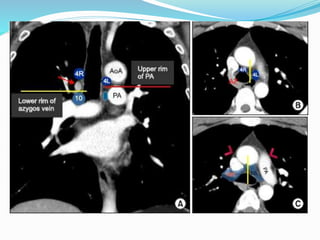

The International Association for the

 14 LN stations reorganized into 7 zones

 Upper zone

 AP zone

 Subcarinal zone